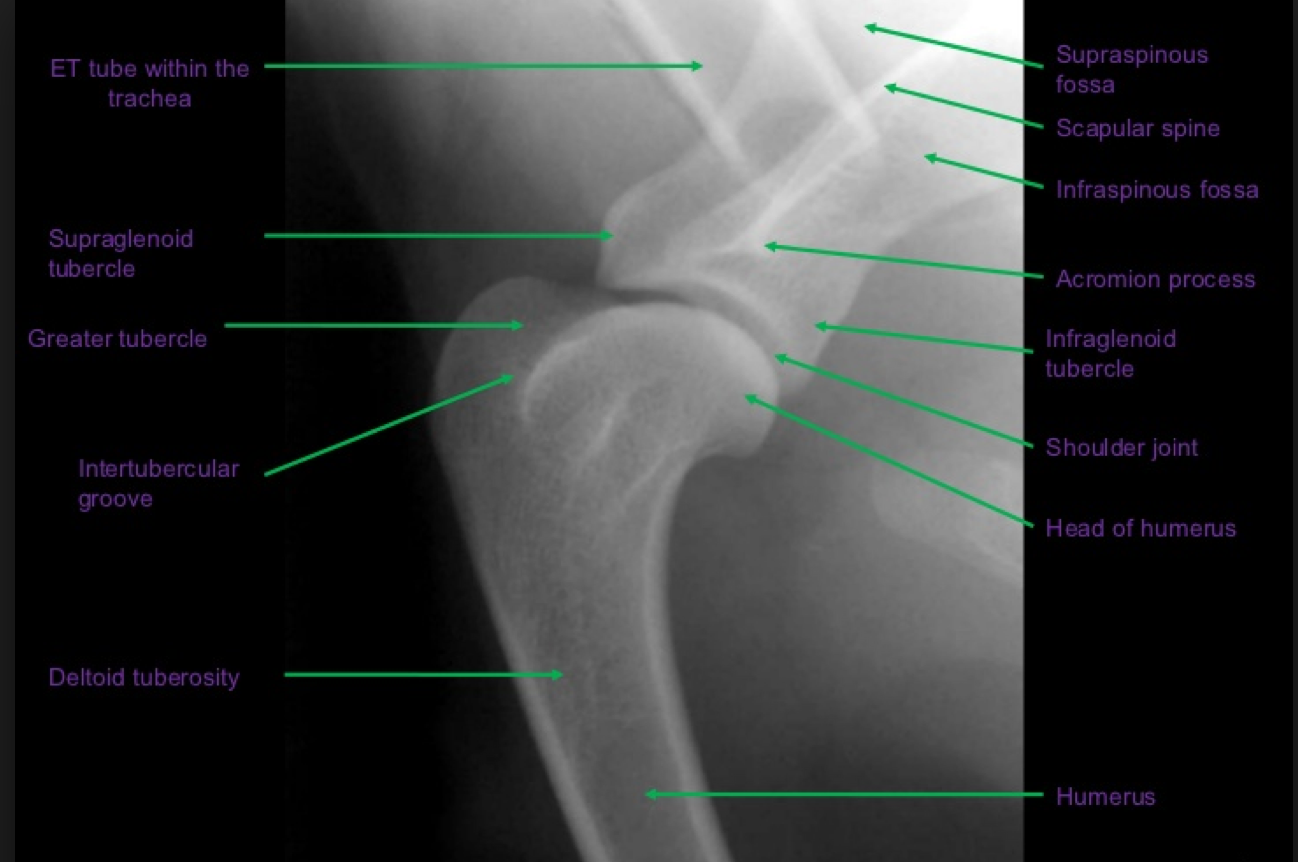

Patient number 245702 - Normal Canine Pelvis

WHAT VIEWS ARE THESE?

Assess Positioning:

•

On the lateral view, use the transverse processes of the vertebrae, and alignment of the two hemipelvises

On the VD view, use the dorsal spinous processes, size and shape in the iliac wings, and symmetry of the

obturator foramina. The femurs should be parallel to each other and parallel to the table (how would you

judge this?). The patellae should be superimposed over the femoral trochlea, within the sagittal plane of the

femur. The fabellae should be roughly located over the femoral cortices.

The lateral projection:

is useful for evaluation of the position of femoral heads compared to acetabulae

is useful for evaluation of the lumbosacral area, especially when looking for the presence of transitional

vertebrae

The VD hip extended projection:

is the official view (by the Australian Veterinary Association, also the OFA in North America, BSAVA in Great

Britain, and FCI in Europe) for screening for hip dysplasia, so correct positioning is very important

is useful for evaluating the position of the femoral heads relative to the acetabulae

is useful for assessment of pelvic fractures

is useful for assessment of other boney pathology of the pelvis

Lateral and ventrodorsal (VD) hip-extended projection.